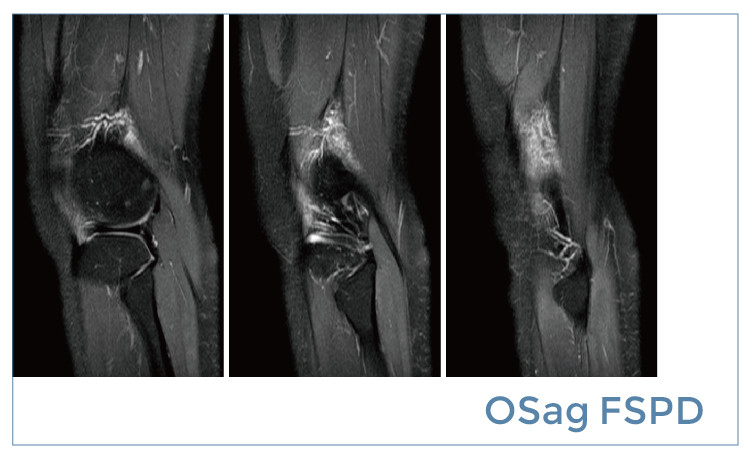

【朗润影像档案】20190510磁共振影像病例结果讨论